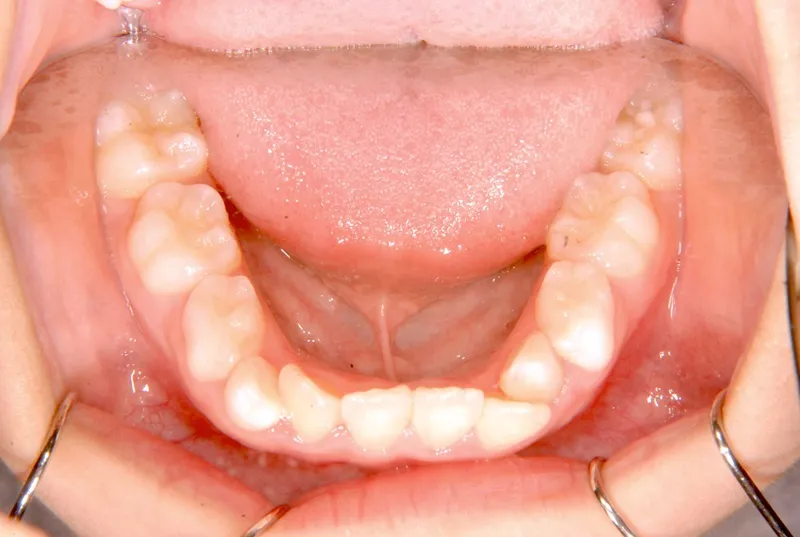

• 初診

初診